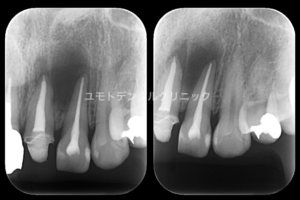

本症例においては透過像の原因歯は左上1番と診断しておりますが、左上2番の症状も該当歯とは別に確認されたため、左上1番の再根管治療後に両歯を外科的歯内療法を行っております。

左上1番再根管治療時

根管充填築造後